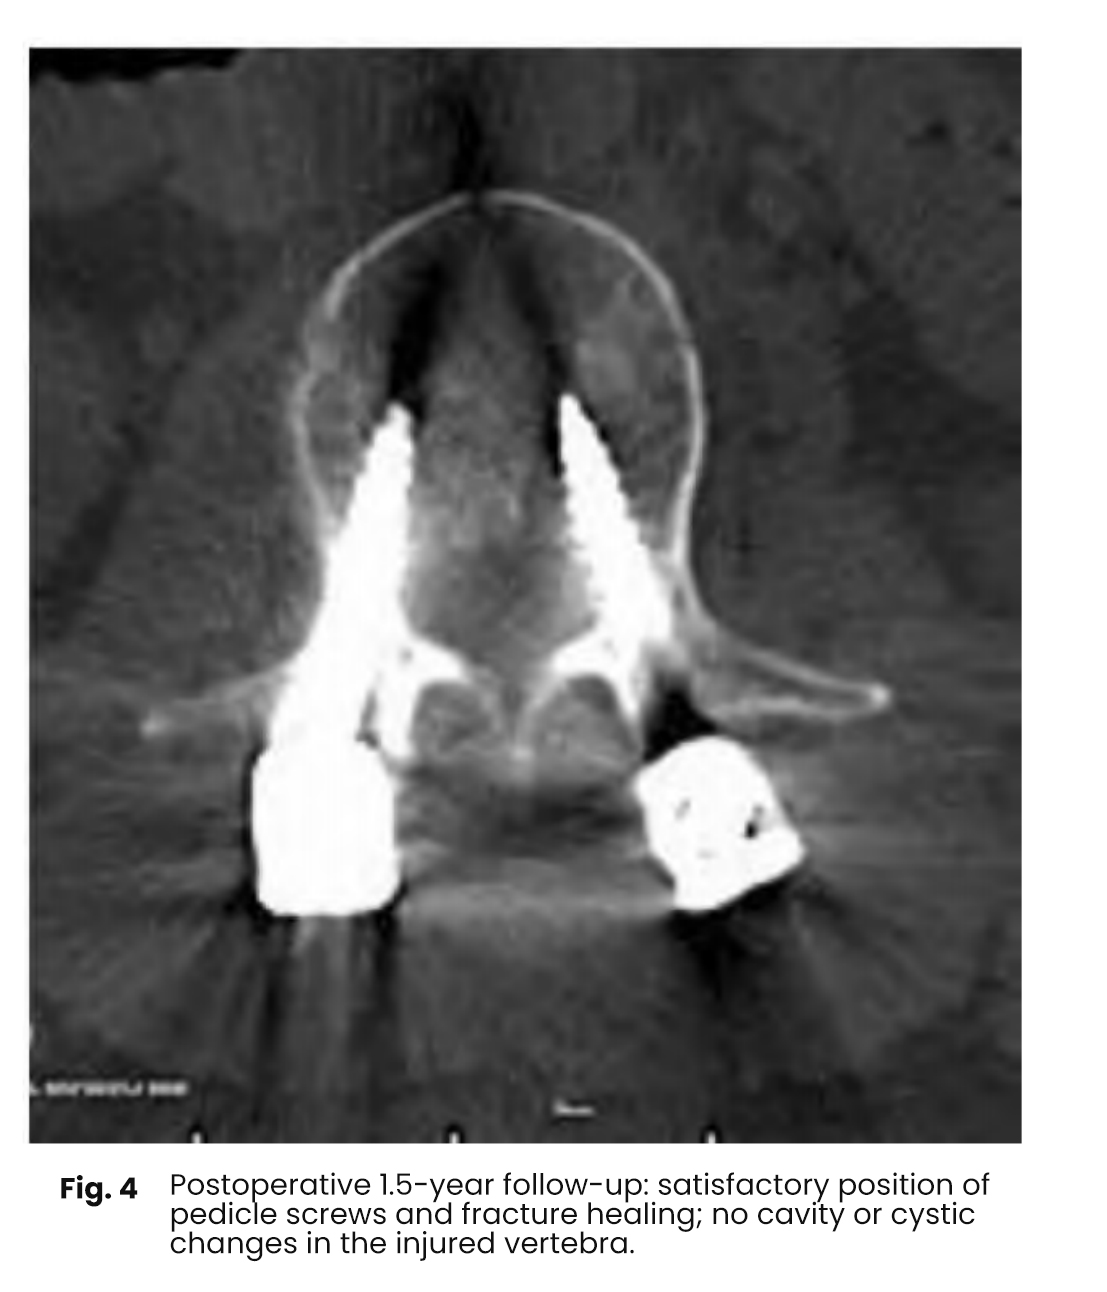

Postoperative follow-up ranged from 1.8 to 2.2 years. Vertebral body height restoration and Cobb angle correction were measured. Fracture healing was evaluated using computed tomography (CT), and postoperative low back pain scores were compared.

Postoperative imaging demonstrated significant improvement in kyphosis compared to preoperative status. All cases showed satisfactory fixation and reduction, with no evidence of vertebral clefts or cystic degeneration within the vertebral body.

Postoperative imaging follow up indicated a significant improvement in kyphosis correction compared to the preoperative state

furthermore fracture healing was observed without any signs of vertebral clefts or cystic cavitation within the vertebral bodies

In all cases involving bone grafting the pedicle screw rod fixation and reduction of the injured vertebrae were satisfactory